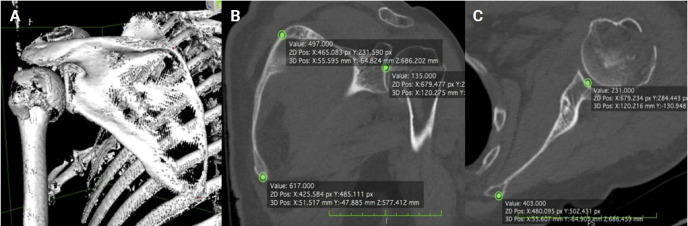

Methods: Shoulder CT scans for arthroplasty were analyzed retrospectively. Glenoid version was measured at the estimated glenoid midpoint using unformatted and formatted 2D-CT in the scapular plane. Measurements from 3D-CT reconstructions using the Corrected Friedman Method were used as the control. Inter- and intra-observer reliability was calculated as well as minimally detectable difference.

Results: Sixty-five CT scans were analyzed (mean age, 61.7 years). Mean glenoid version was -3.48° (standard deviation [SD], 8.7°) on unformatted 2D-CT, -3.27° (SD, 8.15°) on formatted 2D-CT, and -4.25° (SD, 7.92°) on 3D-CT. Although no significant difference in mean values was observed (analysis of variance, P=0.245), formatted 2D-CT measurements were within 6° of 3D-CT in 95.4% of cases versus 83.1% for unformatted 2D-CT (P=0.023). Directional error occurred in 27.7% of unformatted scans and 16.9% of formatted scans. Inter-observer reliability was highest for 3D-CT (intraclass correlation coefficient [ICC]=0.83; 95% CI, 0.74-0.89), and intra-observer agreement was strongest for 3D-CT (ICC=0.91; 95% CI, 0.86-0.94), followed by formatted 2D-CT (ICC=0.83; 95% CI, 0.73-0.89) and unformatted 2D-CT (ICC=0.77; 95% CI, 0.65-0.85).

Conclusions: 3D-CT reconstructions are widely considered the most accurate and reproducible method for glenoid version assessment, supported by multiple comparative imaging studies. Formatted 2D-CT provides a reliable alternative when 3D-CT is unavailable, significantly outperforming unformatted 2D-CT in both agreement with the 3D reference and intra- and inter-observer reliability. Level of evidence: IV.